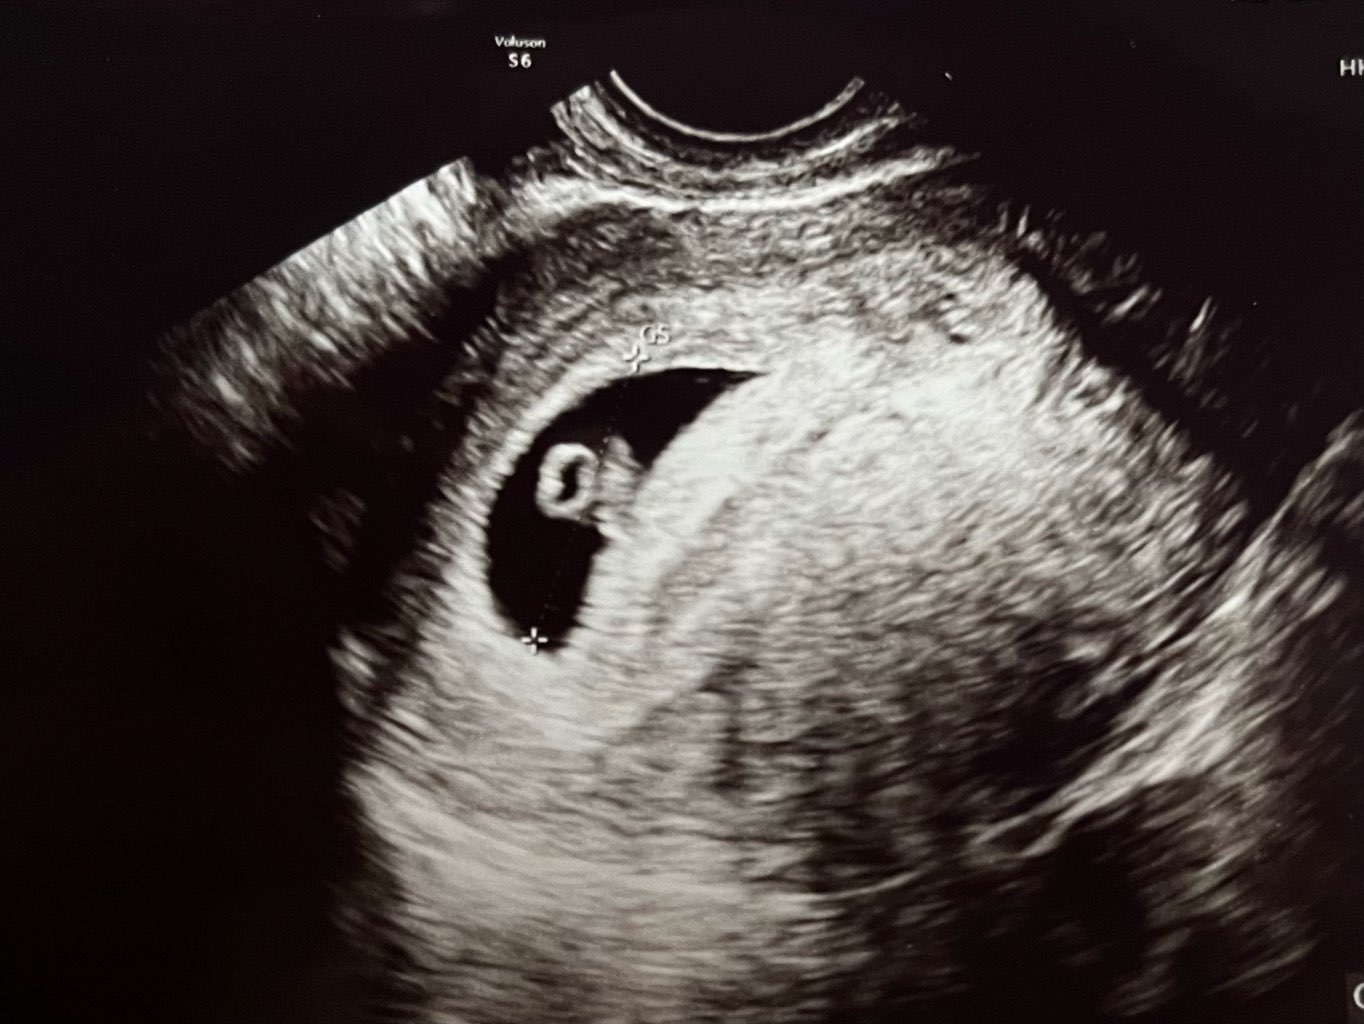

Hej, miałam się odezwać wczoraj, ale dość późno wróciłam od lekarza, a dla mnie w tym momencie każda minuta snu się liczy 😅 Widzieliśmy dzidzię, pięknie biło serduszko. Wygląda na 6+4 lub 6+3 i na ten moment wszystko jest w normie. Mega wzrusz mnie złapał jak zobaczyłam tą małą fasolkę 😍

Wspaniałe wiadomości 😁 uwielbiam zdjęcia USG 😍